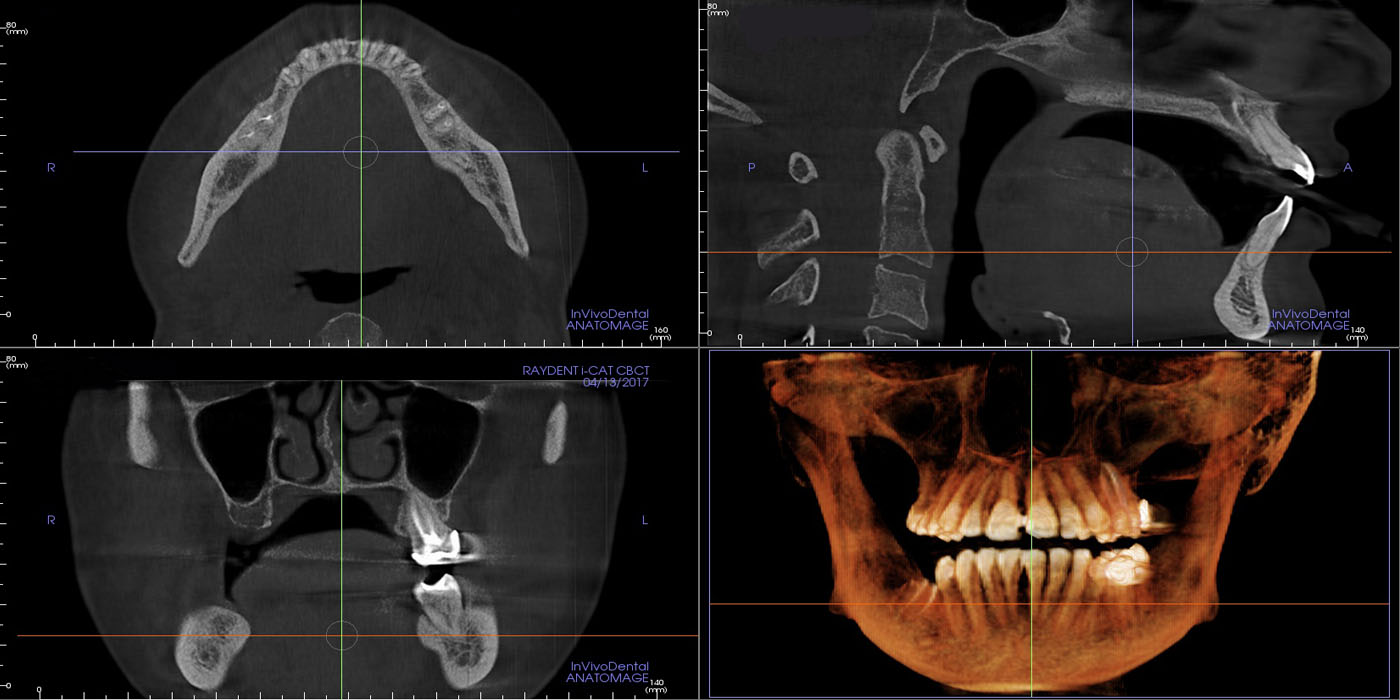

Dental cone beam computed tomography (CT) is a special type of x-ray equipment used when regular dental or facial x-rays are not sufficient. this technology produces three dimensional (3-D) images of teeth, soft tissues, nerve pathways and bone in a single scan.

Dental cone beam CT is commonly used for treatment planning of orthodontic issues. It is also useful for more complex cases that involve:

• Surgical planning for impacted teeth.

• Diagnosing temporomandibular joint disorder (TMJ).

• Accurate placement of dental implants.

• Evaluation of the jaw, sinuses, nerve canals and nasal cavity.

• Determining bone structure and tooth orientation.